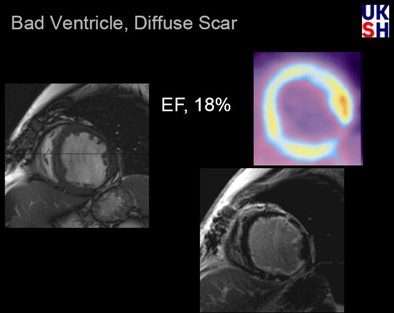

| In a patient with severely impaired LV function (EF 18%), PET reveals a small transmural scar at the inferior lateral wall, as well as an apparent FDG uptake deficit. MRI of the same patient shows a small transmural scar and a large subendocardial scar indicating typical ischemic cardiomyopathy. All data and images courtesy of Dr. Peter Hunold. |